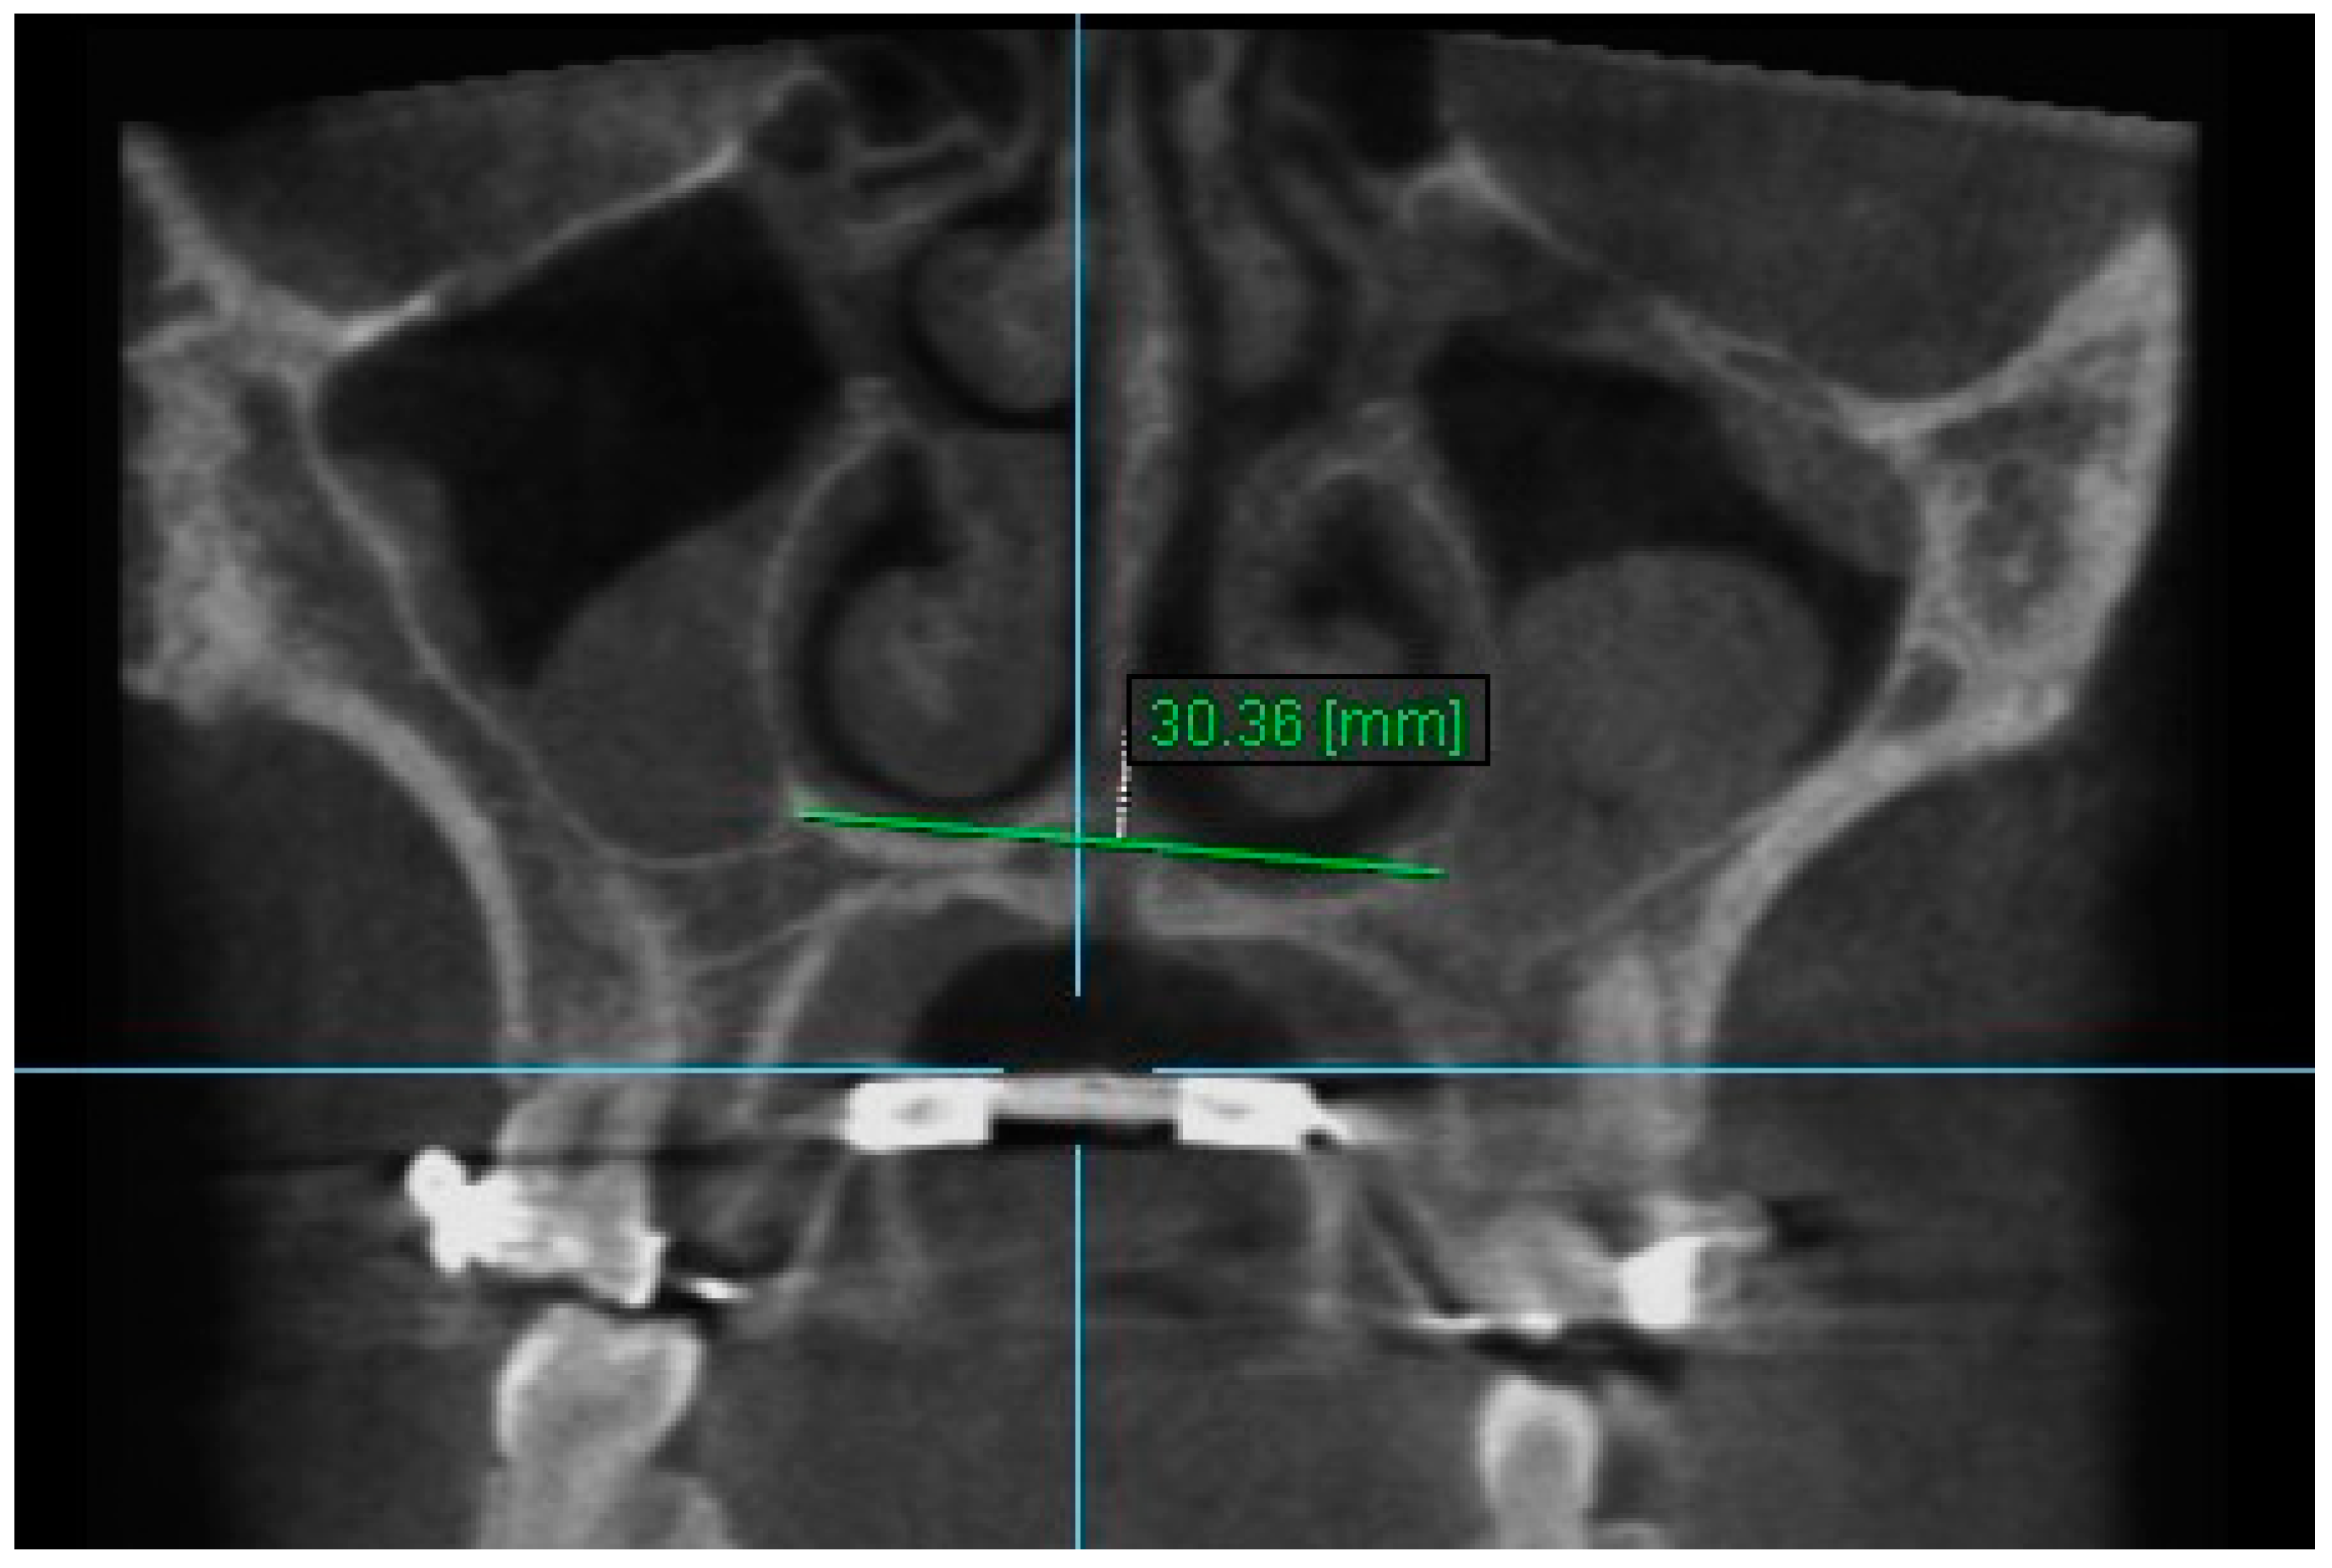

7. Nasal Floor 7: The distance between the junction of anatomical floor of nasal cavity and the medial aspect of the floor ipsilateral sinus on coronal slice through the center of mesial buccal root of the first permanent molar (Figure 9).

Figure 9.

Nasal Floor 7.

Statistically significant differences were found between the mean value of Nasal Floor 7 between all the time intervals, i.e., between T2–T1, T3–T1 and T3–T2 (p < 0.005). An increase in the mean value of Nasal Floor 7 was found immediately after the end of RPE (between T1 and T2), which was statistically significantly decreased 6 months after RPE (between T2 and T3) (Table 8).

Table 8.

Results of the mean differences (mm) of Nasal Floor 7 in the three time intervals.

Statistically significant differences were found between the mean value of Apertures of Midpalatal Sutures 10 and 11 between all the time intervals, i.e., between T2–T1, T3–T1 and T3–T2 (p < 0.005). An increase in the mean values of Apertures of Midpalatal Sutures 10 and 11 were observed immediately after the end of RPE (T2–T1). Statistically significant decreases were found 6 months after RPE (T3–T2). The overall (T3–T1) differences between pre-expansion and 6 months after expansion for Apertures of Midpalatal Sutures 10 and 11 were found statistically significantly increased (Table 11 and Table 12).

The results of this study show that the expansion of the maxilla, shown at the aperture of the midpalatal suture, has a triangular pattern. It was found that the amount of increase was greater (a) at the anterior median palatine suture, (b) bilaterally in the inferior alveolar ridge of the central incisors than the posterior, and (c) bilaterally in at posterior nasal spine (PNS). Similar results to our study have shown that the midpalatal suture has a triangle shape, with the triangle’s vertex in the PNS and its base in perspective [1,2,36,37]. According to Da Silva et al. [38], the palatal suture has its largest width in the anterior region and does not have a parallel opening configuration in the axial plane. Additionally, Kartalian et al. [39] found that after RPE, the midpalatal suture separates in a nonparallel manner in response to expansion forces. The maxilla articulates with unpaired bones, which limits the amount of separation. Caldas et al. [40], studying the effect of rapid maxillary expansion on the nasal cavity assessed with cone-beam computed tomography, concluded that there is a great transverse movement and subsequent separation of the nasal conchae from the nasal septum in both the anterior and posterior sections of the inferior portion of the lateral walls of the nasal cavity after RPE.